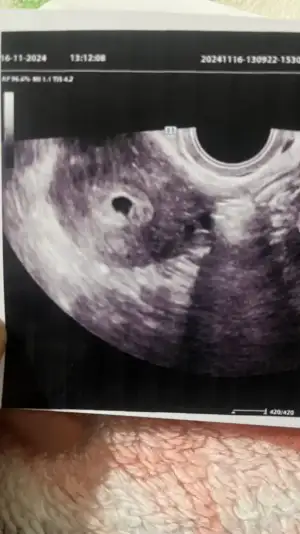

Canım yeni geldim doktordan karından bebegi ve kalp atışını gördük kanamam hala var biraz çogaldı 5 tane igne yazdı yolk kesesi felan oluşmuş ama bebek minnacık daha ilk attıgım ilk gittigim vajinal digeri karından karından bebek görüldü

Eklentiler

• ED27FA84-4B41-48D8-B13D-2ECA17AD2E69.webp

ED27FA84-4B41-48D8-B13D-2ECA17AD2E69.webp

35,2 KB · Görüntüleme: 39